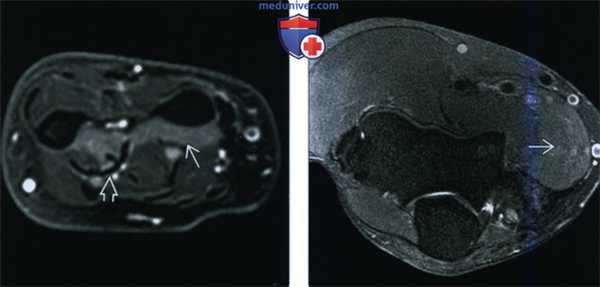

(Слева) На осевой MPT Т2ВИ FS проксимальной трети предплечья определяется незначительное повышение сигнала, указывающее на отек в круглом пронаторе, симптом в результате импиджмента срединного нерва. У пациента две недели назад произошел перелом средней трети диафиза плечевой кости.

(Справа) На осевой MPT Т1ВИ у этого же пациента атрофия круглого пронатора не определяется, так как импиджмент срединного нерва развился относительно недавно. Очевидно, что скоро произойдет жировое замещение мышечных волокон.

(Слева) На боковой рентгенограмме определяется четко очерченный костный вырост, исходящий из переднего кортикального слоя плечевой кости, надмыщелковый отросток. Фиброзный пучок, связка Струзера может протягиваться от кончика этого отростка к медиальному надмыщелку плечевой кости. Срединный нерв проходит под этой связкой, а сокращение прилежащего круглого пронатора может привести к сдавливанию нерва и развитию нейропатии срединного нерва.

(Справа) На передне-задней рентгенограмме у этого же пациента виден надмыщелковый отросток.